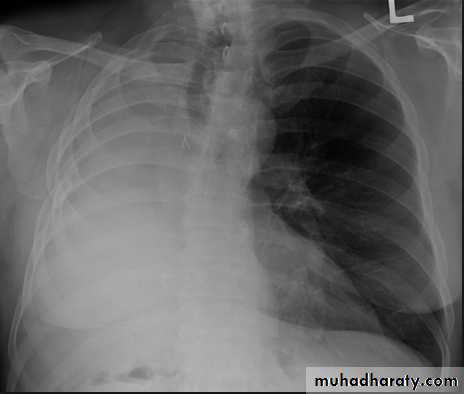

• LOBAR PNEUMONIA

Right lower lobe consolidation - PA. Dense opacification in the right lower zone with effacement of the outline of the right hemidiaphragm.

• Right lower lobe consolidation - Lat.

• The density lies posterior to fthe oblique issure- the position of the lower lobe.